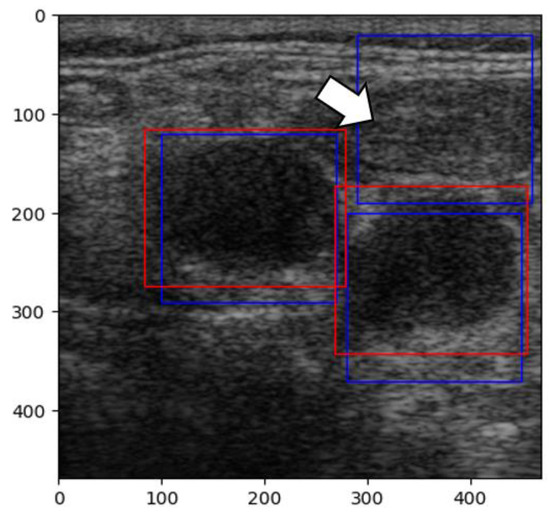

In our second attempt, we rebuilt the CNN using the sliding window technique. The sliding window technique involves moving a fixed or variable-size window through a data structure (an image, in our case) to efficiently solve problems involving continuous subsets of elements. This method efficiently identifies specific criteria present in data [35]. The images were pre-processed by normalizing the pixels’ values between 0 and 1. With this new technique, new challenges arose because of prediction overlap, which prevented us from correctly calculating the IoU between labels and predictions (Figure 11).

Figure 11. Desaturated image with overlapping labels. Red squares: labels. Blue squares: predictions.

Jmms 12 00029 g011

Figure 12. Red squares: labels; blue squares: predictions; arrow: muscle.

Jmms 12 00029 g012